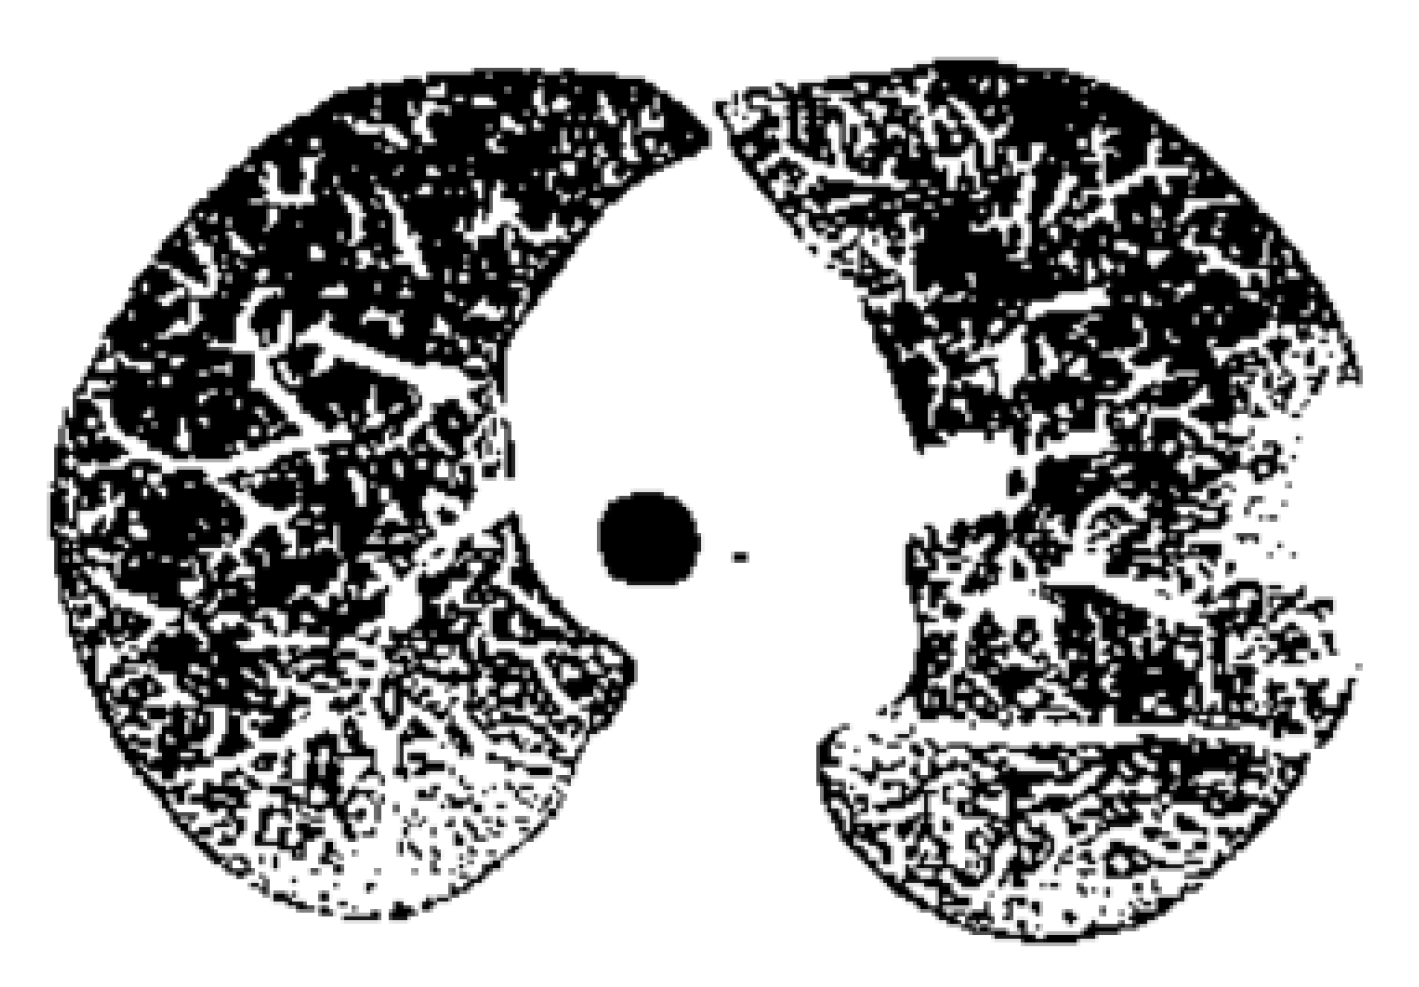

Figure 14 is the binary version of the COVID-19 lung image. Figure 15 represents the box-count algorithm application for the COVID-19 lung image.

Figure 22 is the binary version of the COVID-19 lung image. Figure 23 represents the box-count algorithm application for the COVID-19 lung image.

Figure 22 is the binary version of the non-COVID-19 lung image. Figure 23 represents the box-count algorithm application for the COVID-19 lung image.

Figure 14. Binary version of the COVID-19 lung image.

Figure 22. Binary version of the non-COVID-19 lung image.